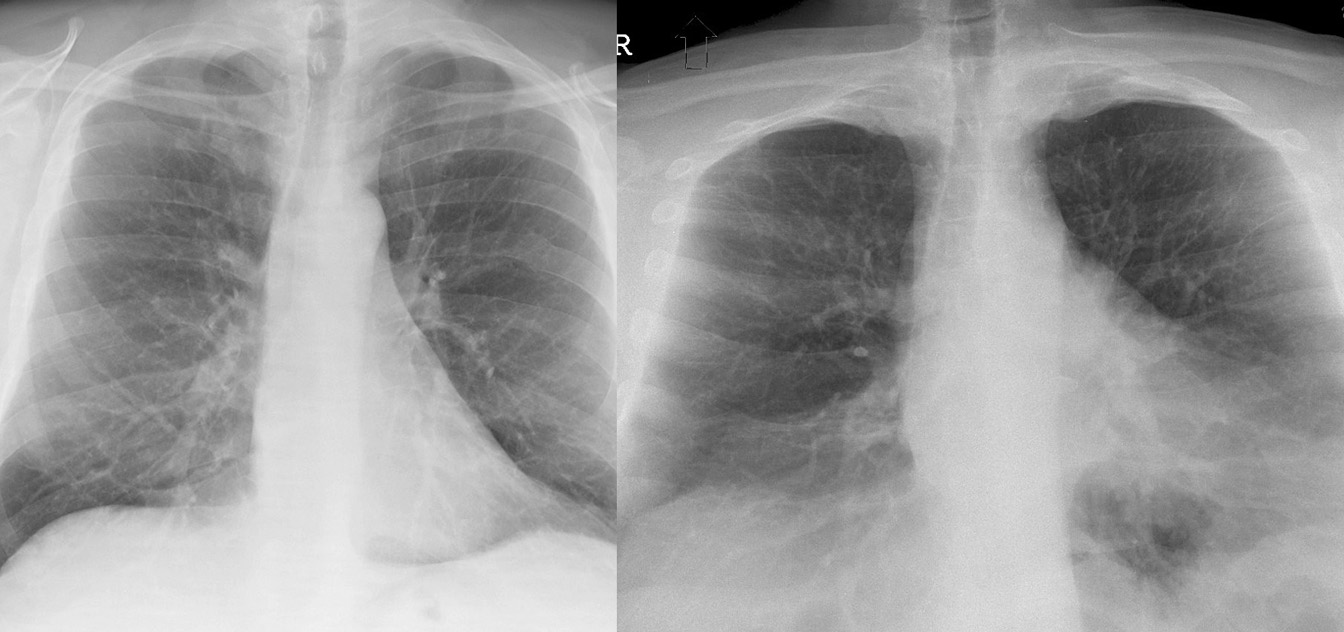

Gallery Normal and Variants Lordotic combo

Lordotic combo